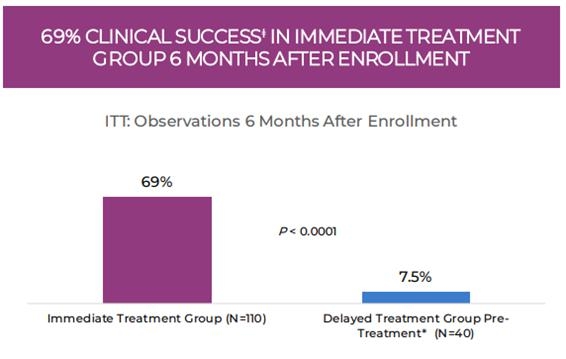

Overall, 310 subjects were enrolled with intent to treat: 246 subjects were randomized to the immediate (ITG, N=171) and delayed (DTG, N=75) treatment groups; 64 subjects were nonrandomized and assigned to the open-label group. Analysis of the primary efficacy endpoint (N=150) demonstrated clinical success (complete and/or substantial response) in 69% of patients in the ITG 6 months after enrollment, while 7.5% of patients in the DTG experienced spontaneous regression of a LM during this time interval (p < 0.0001)). When the results were analyzed by lesion type across all treatment groups, a successful outcome was observed in 84% and 60% of patients with macrocystic and mixed-cystic LM, respectively. None of the patients with microcystic LM demonstrated clinical success with OK-432 therapy. The results of the retrospective analysis were consistent with the results observed in the original analysis (Smith et al. 2009).

Figure 1: 69% of patients in the immediate treatment group had a complete or substantial response to OK-432, meeting the primary endpoint, while 7.5% of patients in the delayed treatment group had a complete or substantial response after six months of observation and before treatment.

| ǂ | Clinical Success was defined as complete or substantial response. |

| * | Reflects data prior to dosing with OK-432. After dosing, the clinical success rate was 66%, which was not statistically different from the ITG. |